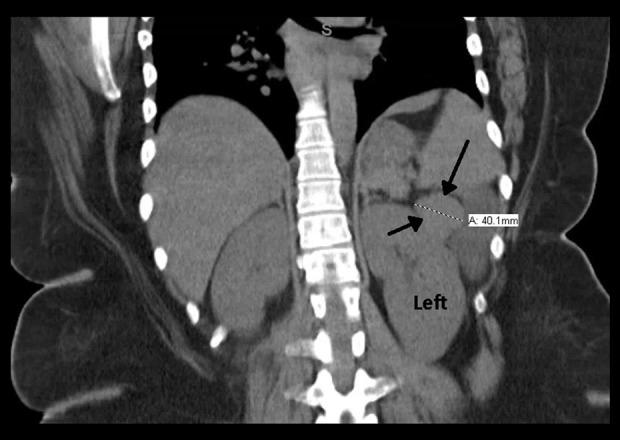

BACKGROUND VIPomas are rare neuroendocrine tumors typically located in the pancreas. The majority of cases autonomously secret vasoactive intestinal polypeptide (VIP), which can result in profuse, refractory, watery diarrhea. The fluid and electrolyte imbalance can progress to dehydration and profound hypokalemia, resulting in the watery diarrhea, hypokalemia, achlorhydria (WDHA) syndrome. One previous case of a pancreatic VIPoma progressing to hypokalemic rhabdomyolysis has been described. CASE REPORT A 33-year-old woman presented with 3 months of progressive, refractory diarrhea and weakness. Her serum VIP level was elevated and imaging discovered a mass in the region of the pancreatic tail. Laparoscopic partial pancreatic resection was performed and a 3.7-cm diameter, solitary stage T2 N0 M0, well-differentiated carcinoma was removed. CONCLUSIONS A high index of suspicion is important when diagnosing chronic diarrhea. Minimally invasive surgery is an option in the surgical treatment of pancreatic VIPoma.

背景 血管活性肠肽瘤(VIPoma)是一种罕见的神经内分泌肿瘤,通常位于胰腺。大多数病例会自主分泌血管活性肠肽(VIP),这可导致大量、难治性水样腹泻。体液和电解质失衡可发展为脱水和严重低钾血症,导致水样腹泻、低钾血症、无胃酸(WDHA)综合征。此前曾有一例胰腺VIPoma进展为低钾性横纹肌溶解症的病例报道。病例报告 一名33岁女性出现3个月的进行性、难治性腹泻和乏力。她的血清VIP水平升高,影像学检查发现胰尾区域有一个肿块。进行了腹腔镜胰腺部分切除术,切除了一个直径3.7厘米、孤立的T2 N0 M0期、高分化癌。结论 在诊断慢性腹泻时,高度的怀疑指数很重要。微创手术是胰腺VIPoma手术治疗的一种选择。